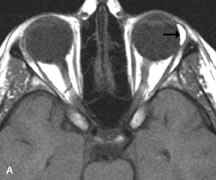

On MRI, uveal melanomas have a typical appearance that helps to differentiate them from other primary and secondary intraocular tumors as well as choroidal detachments. Pigmented melanomas are hyperintense on Tl-weighted images, hypointense on T2-weighted studies, and hyperintense on proton density–weighted examinations (Fig. 24).30,31,50,80–82 These signal characteristics have been attributed to the paramagnetic properties of melanin because of stable free radicals that shorten the T1 and T2 relaxation times. Moderate enhancement is seen on postgadolinium T2-weighted images. Gadolinium-enhanced T1-weighted images are particularly sensitive in detecting choroidal melanomas.83 MRI may be less sensitive in detecting extrascleral extension of tumor than echography performed by an experienced ultrasonographer.84

Fig. 24. A. T1- and (B) T2-weighted MR scans demonstrate a small nodular intraocular mass (arrows) that is very hyperintense on the T1-weighted scan and hypointense on the T2-weighted image. This signal intensity pattern is due to the presence of free radicals within melanin granules. C and D. Postcontrast fat-suppressed T1-weighted scans demonstrate homogeneous intense enhancement of the lesion and no evidence of seleral penetration or optic nerve invasion.